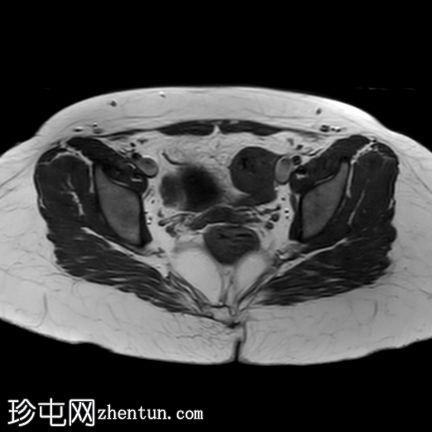

轴位

T1加权像

T2加权像

轴位T2加权像

薄层扫描

盆腔两侧可见两个残角,位于双侧卵巢尾侧。可见一条水平带连接两个残角。左侧残角呈腔状,右侧残角呈非腔状。

可见宫颈阴道发育不全,从两个残角延伸出少量发育不良的宫颈组织带。

双侧卵巢功能正常,可见卵泡。